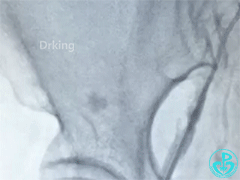

突发情况!术后一小时腹部包块,血压下降,血红蛋白下降,再次导管室!

股动脉造影: